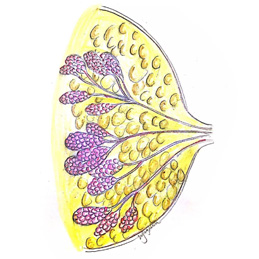

…ωΑ© «‘¥Ή‘…ω‘ύΒΡΕώ–‘÷ΉΝωΘ§≥ΘΦϊ”Ύ÷–άœΡξ»Υ»ΚΓΘ‘γΤΎΈόΟςœ‘÷ΔΉ¥Θ§ΆμΤΎΩ…Ρή±μœ÷ΈΣ―ΣΡρΓΔ―ϋΆ¥ΜρΗΙ≤Ω÷ΉΩιΓΘ‘γΤΎΖΔœ÷Ε‘ΗΡ…Τ‘ΛΚσ÷ΝΙΊ÷Ί“ΣΘ§Ε®ΤΎΧεΦλ”–÷ζ”Ύ‘γΤΎ’οΕœ